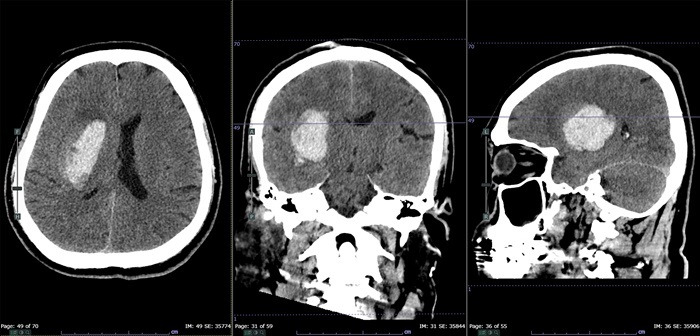

뇌출혈이란 두개골 내에 출혈이 있어 생기는 모든 변화를 말하는 것으로 출혈성 뇌졸중이라고도 한다.

뇌출혈은 여러 가지 방법으로 구분하고 있으나 크게 외상에 의한 출혈과 자발성 출혈로 구분할 수 있다.

외상에 의한 출혈은 급성 경막하 출혈, 만성 경막하 출혈, 경막외 출혈 등 두부 외상과 직간접적으로 연관이 있는 출혈을 말한다. 자발성 뇌출혈이란 다음과 같은 질환 중에 뇌출혈을 일으킨 것을 말한다.

고혈압성 뇌출혈은 만성 고혈압과 관련 있는 경우가 많으며, 혈압 상승의 정도 및 기간과 관련이 있다. 또 고혈압성 뇌출혈은 출혈 부위에 따라 피각 출혈, 시상 출혈, 피질하 출혈, 뇌교 출혈, 소뇌 출혈로 나눌 수 있다.

고혈압성 뇌출혈은 뇌졸중 가운데 약 10%를 차지하며 나이, 고혈압, 뇌경색, 관상동맥 질환, 당뇨 등이 그 위험인자로 알려져 있다. 대부분 50대에서 60대에 주로 발생하며 성별의 차이는 거의 없다. 고혈압성 뇌출혈은 뇌내출혈을 초래하여 약 40% 정도의 사망률을 보인다.

뇌동맥류에 의한 출혈은 90% 정도가 뇌주막하 출혈로 발생하며, 사람이 일생에서 가장 극심한 두통을 호소하는 것으로 알려져 있다.